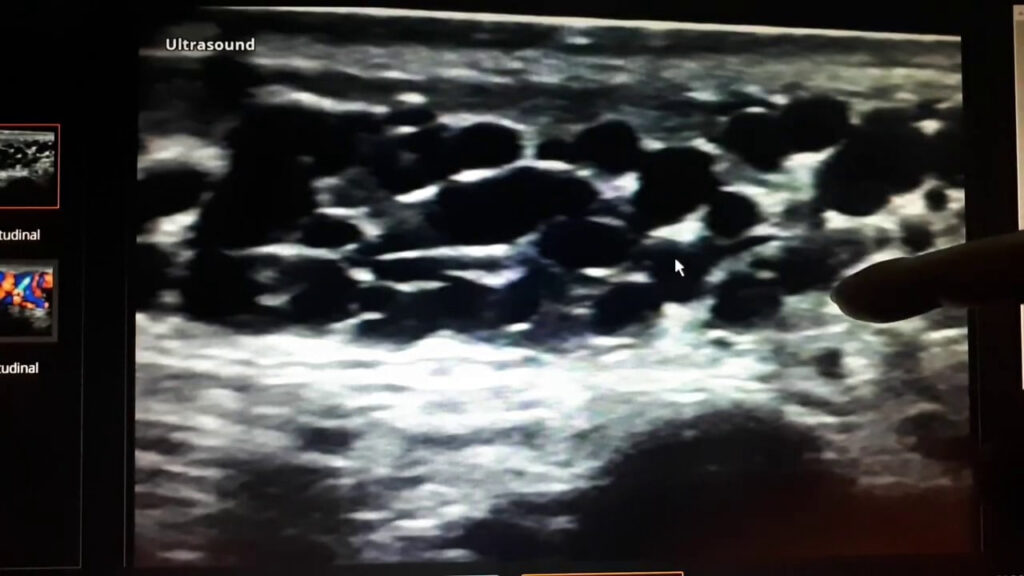

Доказовим методом у діагностиці варикозу мошонки є УЗД мошонки. Також лікар уролог-андролог може під час прийому оцінити пальпаторно (пальцевим методом) розширення вен мошонки, що свідчить про потребу в проведенні УЗД мошонки.

Оцінка результатів УЗД мошонки – проводиться проба Вальсальви:

- Пацієнта просять зробити глибокий вдих, затримати дихання, напружити м’язи живота. У цей момент лікар перевіряє вени на УЗД, використовуючи доплер, і оцінює, чи відбувається зворотний відтік крові (рефлюкс) у венах яєчок.

- За позитивного рефлюксу – якщо під час проби Вальсальви проявляється зворотний відтік крові у вени, це підтверджує наявність варикоцеле.